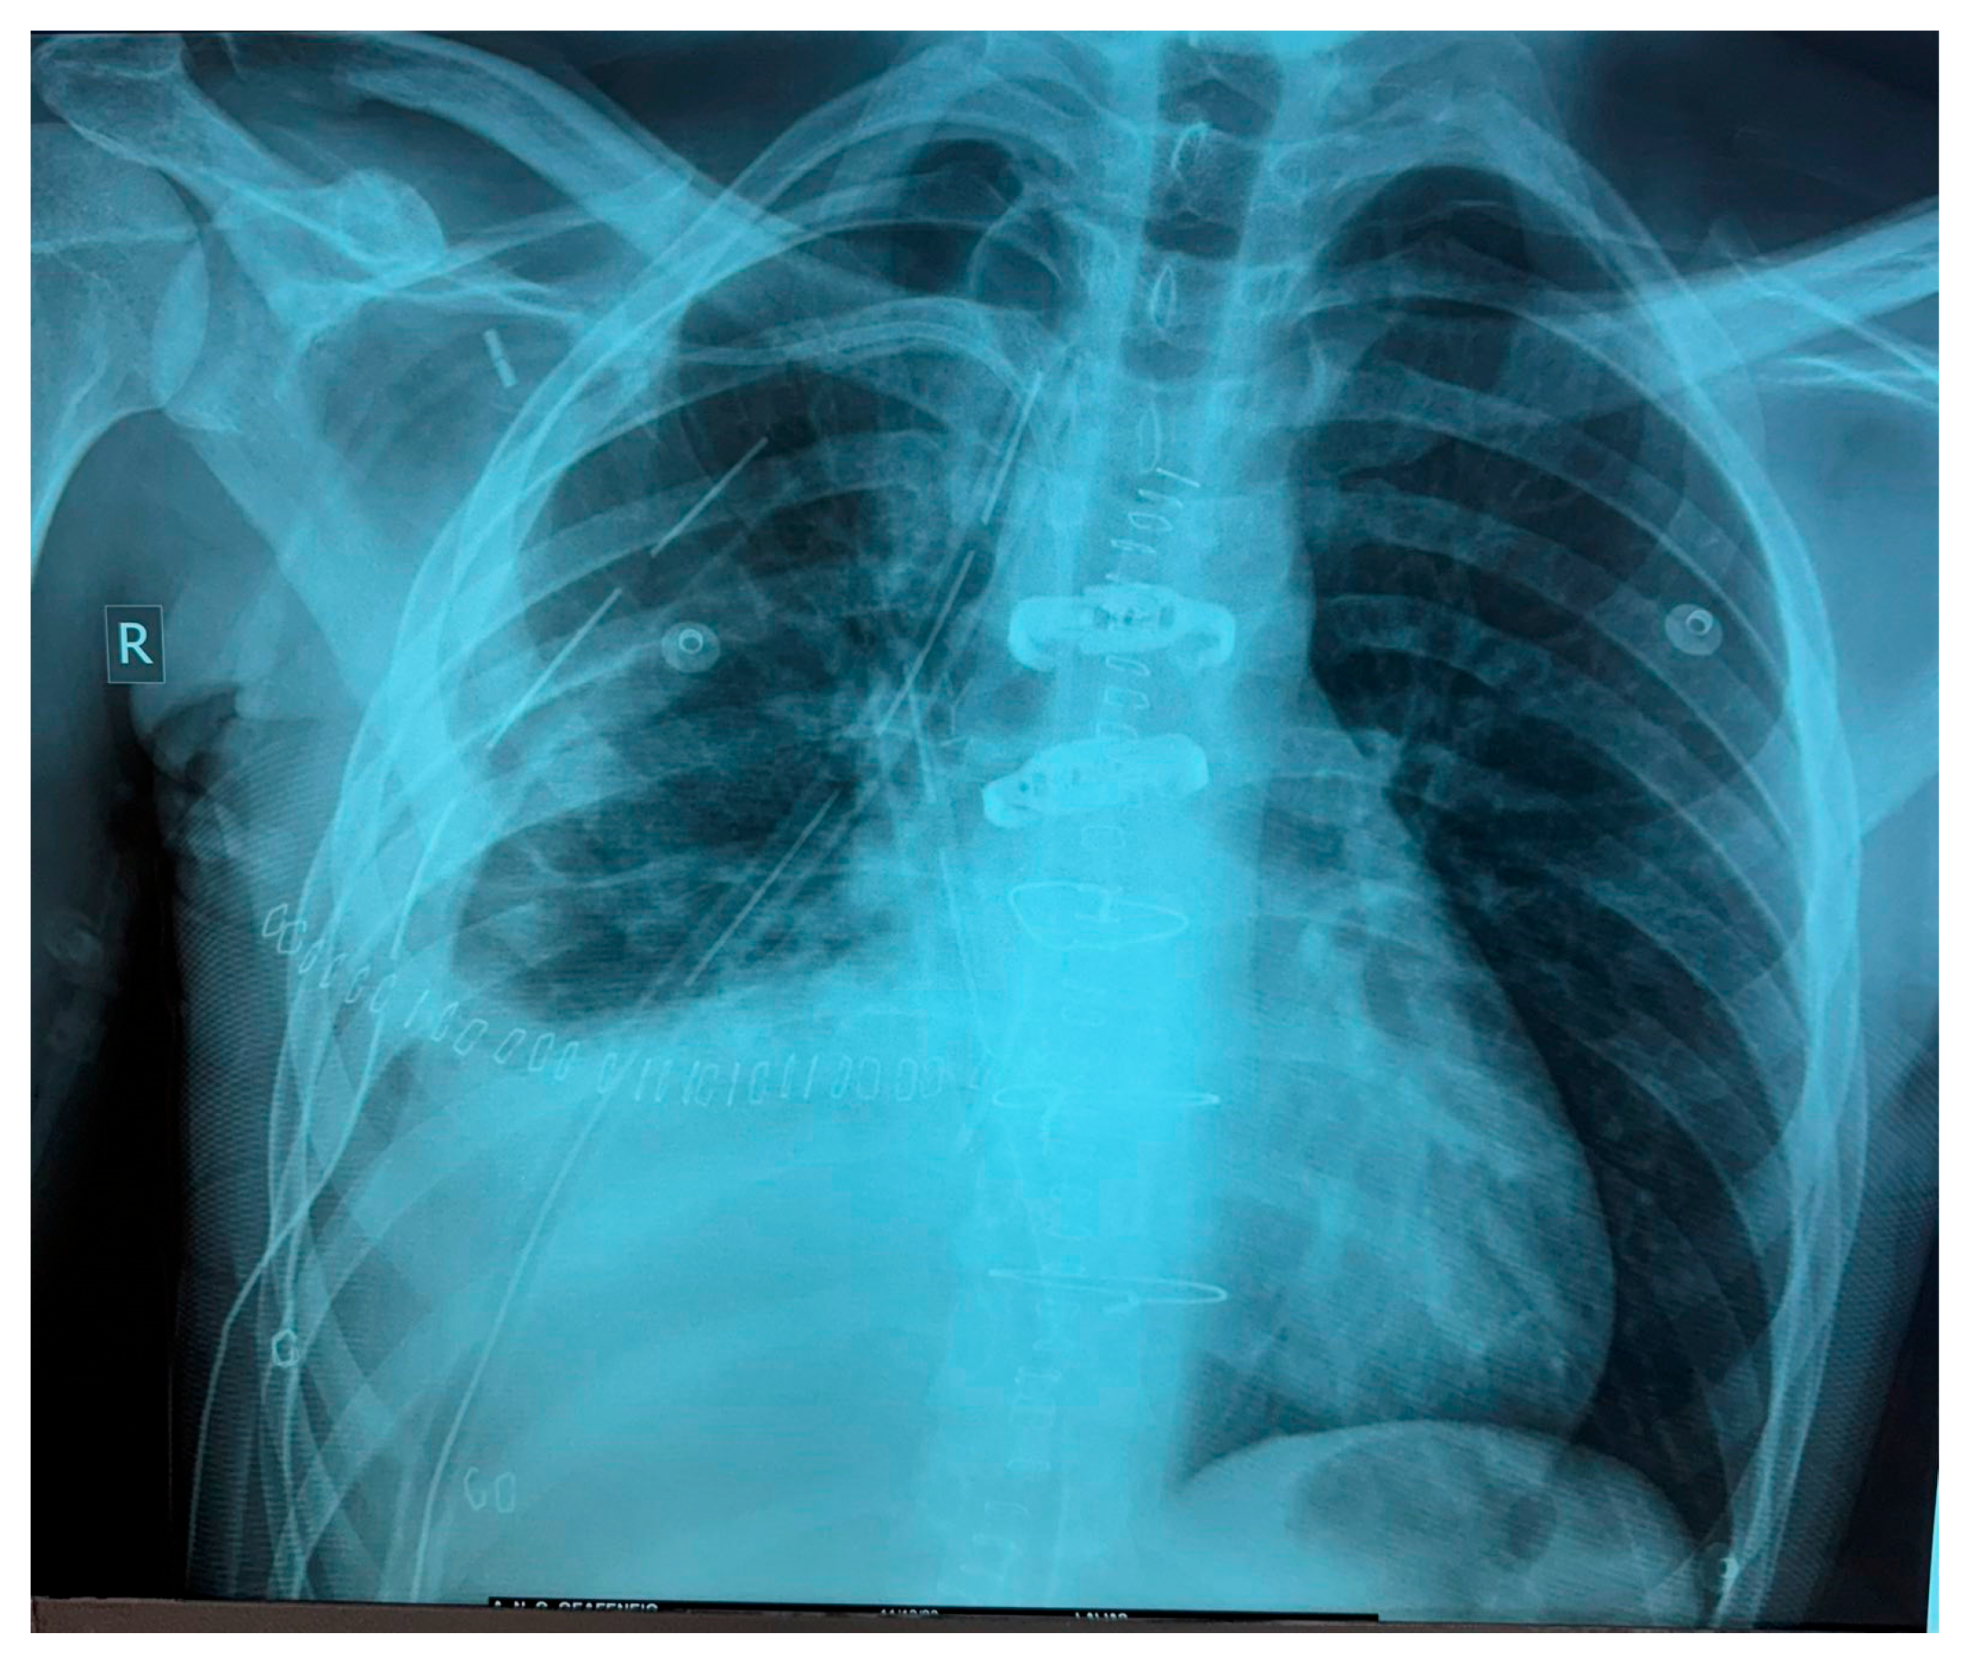

The following imaging procedures that took place, such as high-resolution chest computer tomography (chest CT) and positron emission tomography–computed tomography (PET-CT), confirmed the presence of an heterogenous anterior and middle mediastinal voluminous formation, extending into the (R) lung cavity, with quite notable size measurements (DMax: ~11 cm × 10 cm × 13 cm), a significant standardized uptake value (SUV: 8.7), areas of cystic degeneration, necrosis, and associated pleural effusion (Figure 1).

The tumor applied additional pressure on both (R) heart chambers, causing tracheobronchial compression and mediastinal shift. The PET-CT imaging process identified hypermetabolic foci in mediastinal lymph nodes and neighboring osseous structures, suggesting additional metastatic spread.

Figure 1. Initial preoperative PET-CT imaging control.